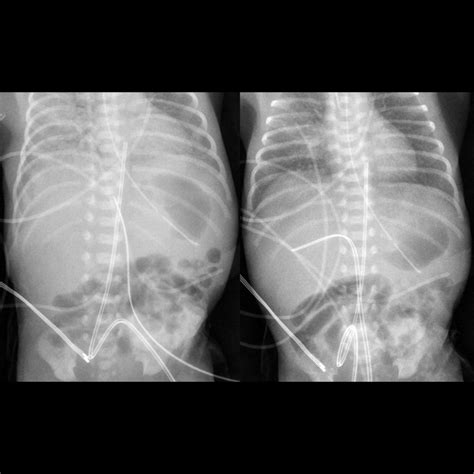

3. Insertion: The catheter is gently inserted into the umbilical vein, which is identified by its larger size and bluish color compared to the arteries. The catheter is advanced until it reaches the desired position, typically confirmed by ultrasound or X-ray.

5. Verification: The position of the catheter is verified using imaging techniques to ensure it is correctly placed in the inferior vena cava.

• Malposition: Incorrect placement of the catheter can lead to ineffective therapy or complications such as arrhythmias.